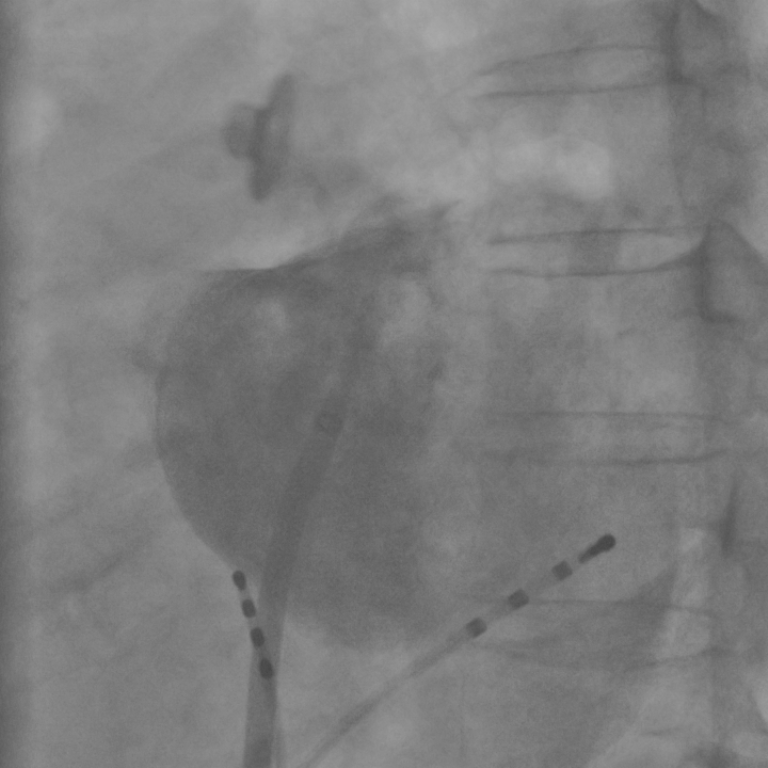

The contrasted area is found based on a difference image (DSA) , involving a frame that contains contrast agent and an uncontrasted frame . To distinguish between contrasted and uncontrasted frames, either manual annotation, a threshold based method e.g. the method described in [10] or an automatic contrast detection [6] can be used. Depending on the chosen contrasted frame , may contain artifacts due to motion of the diaphragm or from catheters if they are at different positions in and . Such motion artifacts depend, unlike the information about contrast agent, to a large degree on the choice of . For example, if the catheters in are at the same position as in , their intensities cancel out in the subtraction image. Otherwise, has high positive values at the position of the catheter in and high negative values at the position of the catheter in . To keep motion artifacts to a minimum, we propose a best reference selection, which chooses an appropriate reference frame that matches the chosen contrasted frame as much as possible. Out of all uncontrasted frames, that frame is selected which minimizes the -norm of the resulting DSA image

| (1) |

By following Eq. 1, we get frames for which the catheters and the diaphragm cancel out as much as possible. See Figure 2 for an example. In , only pixels with positive values contain contrast agent. To extract them, we set the intensity of pixels with negative value to 0. Afterwards, we compute a filtered image by applying a median filter with a large kernel size. Smaller structures, e.g., caused by motion artifacts that remained despite the optimized choice of , do not pass this filter, and the noise in the contrasted area is reduced as well. Finally, a binary image of the filtered image is computed using a threshold at where and denote the mean and standard deviation of , respectively. Thus, a contrasted pixel is indicated by .